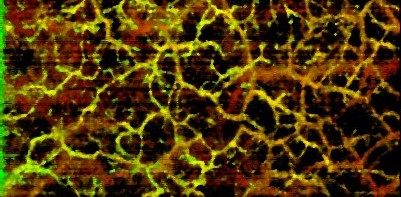

OCT angiography scans captured with the Cobra-S 800 exhibit reduced motion artifacts due to the high speed of imaging, in addition to high resolution.

Better roll-off performance and greater camera sensitivity enables visualization of deep vasculature in the dermis.